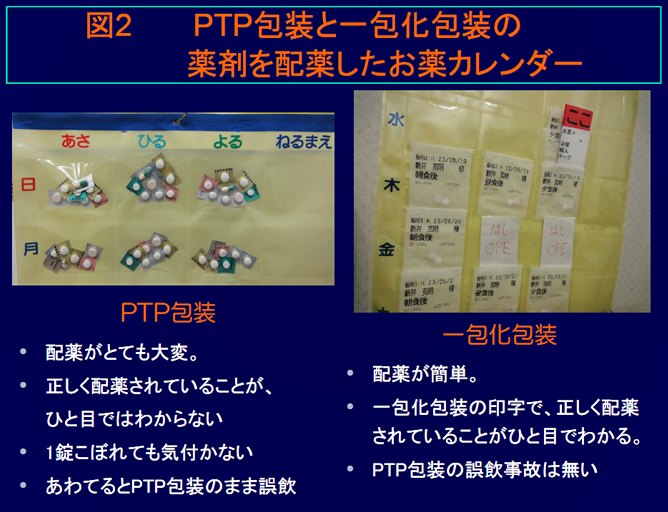

薬のptpシートを1錠ずつバラバラにするのは止めて下さい 第4報

Http Www Jshp Or Jp Cont 10 0922 5 Pdf